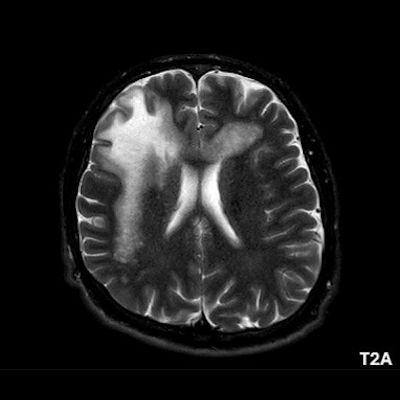

1. A) Aksiyel T2A görüntülerde bilateral sağda belirgin frontoparietal subkortikal ve derin periventriküler beyaz cevherde subkortikal U fiberleri boyunca yerleşimli sinyal artımları (oklar) izlendi.  Tarifli alanlar aksiyel T1A serilerde hipointens görünümde (oklar) izlendi.

1. PML’de MRG bulguları genellikle multifokal, asimetrik periventriküler ve subkortikal beyaz cevher tutulumu şeklindedir. Subkortikal U-fiberleri sıklıkla tutulur, özellikle parietooksipital bölgelerde belirgin lezyon eğilimi vardır.

2. T1 ağırlıklı görüntülerde tutulan bölgeler hipointens, T2A’da ise hiperintens izlenir. Ana lezyon çevresinde çok sayıda noktasal (milkyway) sinyal artımları görülebilir. Ayrıca spleniumu çaprazlayan parietooksipital sinyal değişiklikleri (barbell bulgusu) ve dentat nukleusu koruyarak serebellar beyaz cevher tutulumu (shrimp bulgusu) da tanımlanmıştır.

4. Bizim hastamızda bilinen HIV enfeksiyonu mevcuttu ve yapılan kraniyal MR görüntülemede multifokal, asimetrik, periventriküler ve subkortikal beyaz cevherde yerleşimli, kitle etkisi göstermeyen ve kontrastlanmayan lezyonlar izlendi. Lezyonların subkortikal U-fiberleri tutması ve özellikle parieto-oksipital bölgelerde belirgin olması nedeniyle ön planda PML düşünüldü. Histopatolojik tetkik ile PML tanısı doğrulandı.